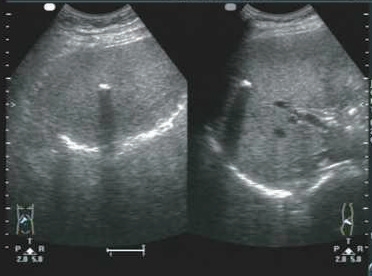

1)胆囊腔内高/强回声团。胆囊结石与周围液性胆汁声阻抗差较大,使得胆囊结石的边界可清楚显现。由于结石本身的形状、结构和成分不同,其回声形态可有较大差别。结构较致密且表面较光滑的结石,表现为新月形强回声(图5-6);结构较松散的结石,由于透声性好,结石的全貌均可被显示,呈满月形强回声(图5-7);数个堆积在一起的小结石可产生堆积状、沙堆状强回声(图5-8)。

图5-6 胆囊致密结石(新月形)及声影

图5-7 胆囊疏松结石(满月形)及声影

图5-8 胆囊多发结石(堆积状、沙堆状)及声影

2)强回声团伴有声影。结石强回声后方,与声束入射方向一致的无回声暗带,即声影(图5-7)。它是结石对声能的吸收及反射的综合效应。典型的声影对确定胆结石比强回声更具有特异性。直径<0.3 cm的小结石,由于腹部探头声束波长产生绕射,声影不明显。